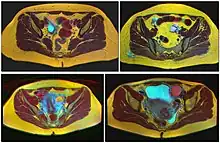

Transvaginal ultrasonography of a hemorrhagic ovarian cyst, probably originating from a corpus luteum cyst. The coagulating blood gives the content a cobweb-like appearance.

Transvaginal ultrasonography of a hemorrhagic ovarian cyst, probably originating from a corpus luteum cyst. The coagulating blood gives the content a cobweb-like appearance.